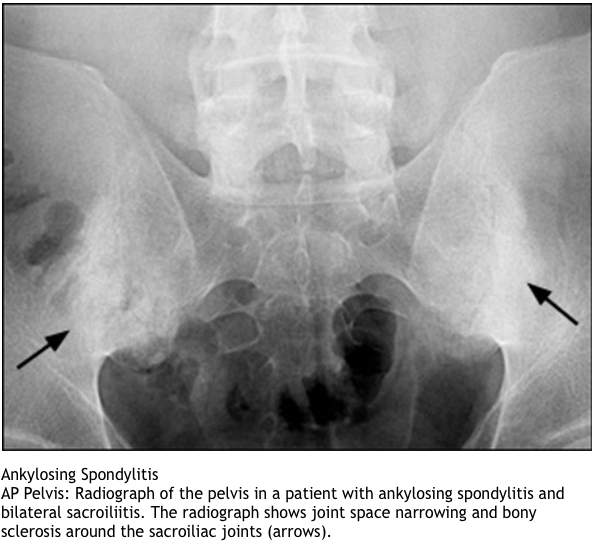

What imaging is useful in dx ank spon?

marginal syndesmophytes, bamboo spine, ossificiation of disc space, osteopenia, strong assoc wiht HLA b27, younger pts, bilateral sacroilitis